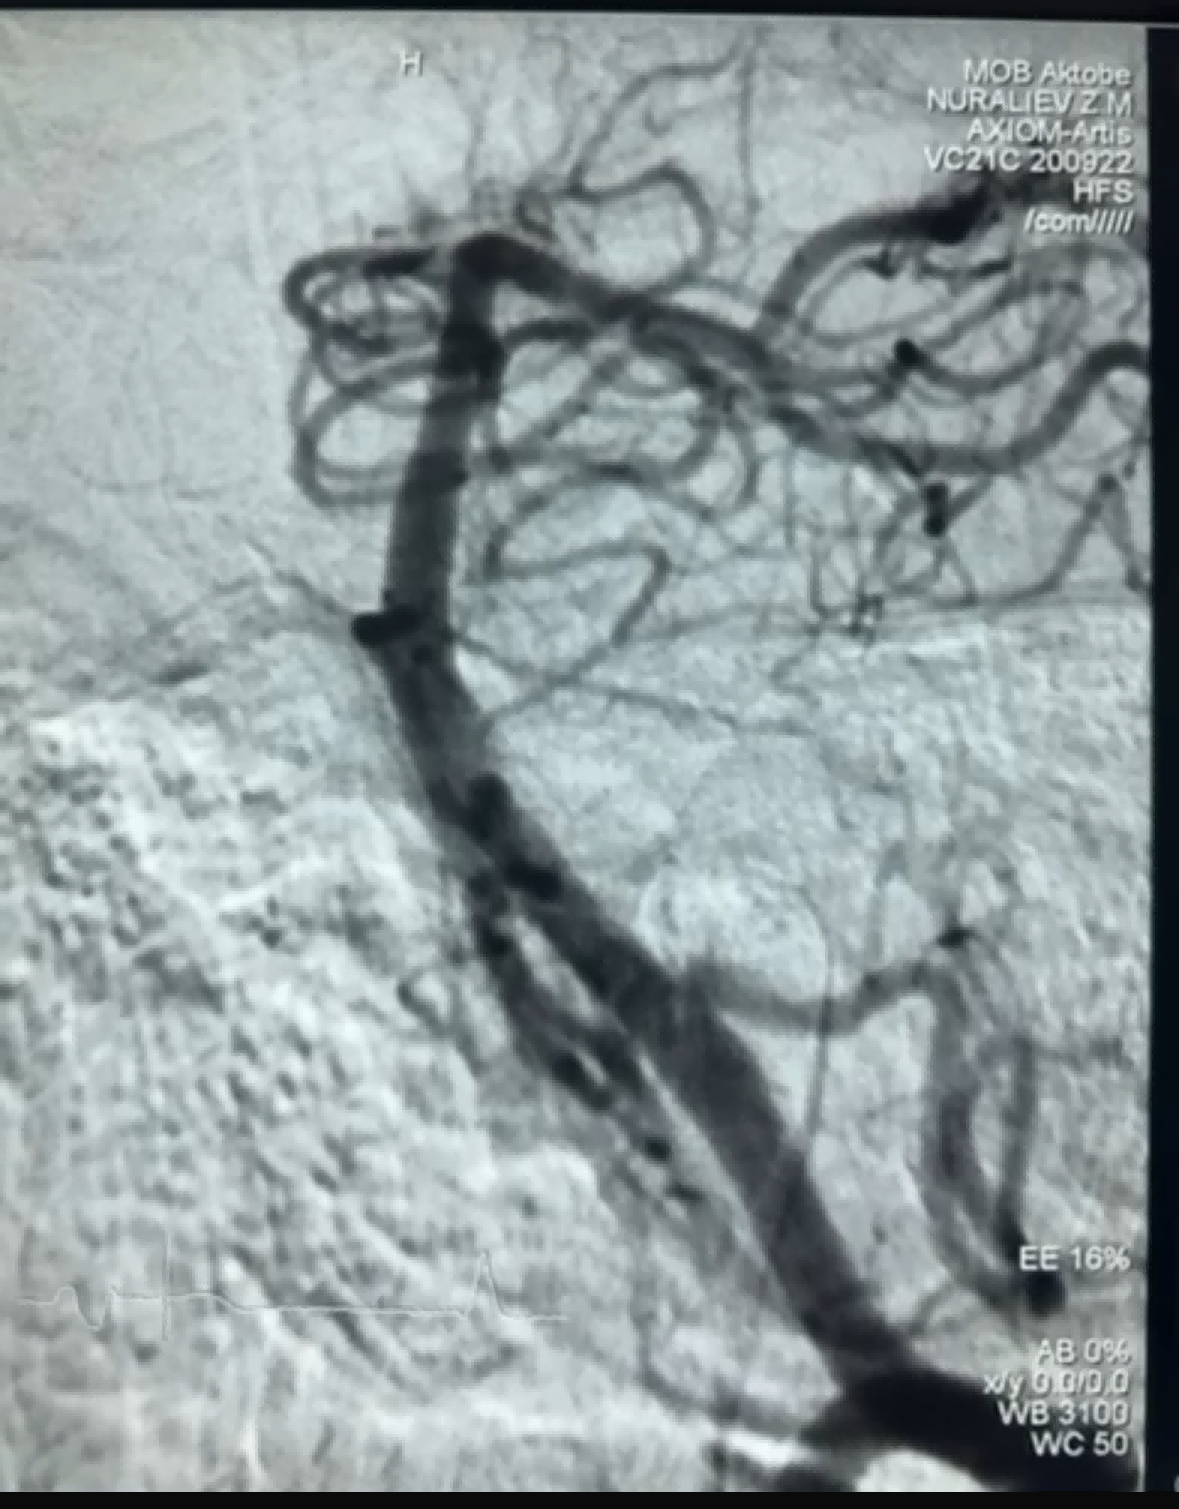

সম্প্রতি, নিউরোসেফ মেডিকেল কোং লিমিটেডের ড্রেজার স্টেন্ট রিট্রিভার ব্যবহার করে একটি সফল থ্রম্বেকটমি কেস হয়েছে। ড্রেজার স্টেন্ট রিট্রিভারের একটি অ-আক্রমণকারী নরম টিপ রয়েছে, যা অন্তরঙ্গ ক্ষতির ঝুঁকি অনেকাংশে কমিয়ে দেয় এবং একটি অনন্য বিশেষ আকৃতির গর্ত রয়েছে। এমন নকশা যা রক্তের জমাট বাঁধার মাধ্যমে প্রধানত ফাঁক পরিবর্তন করে।